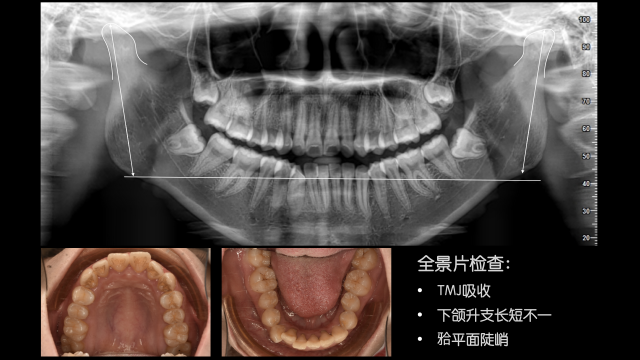

术后总结